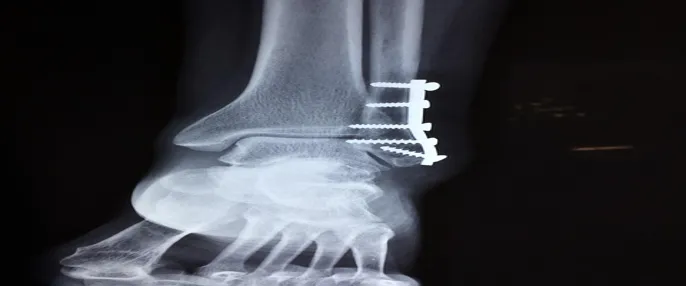

갈비뼈 골절을 진단하기 위해 가장 일반적으로 사용되는 방법은 X-ray 촬영입니다. X-ray는 뼈의 상태를 확인할 수 있는 유용한 도구로서, 갈비뼈의 골절 유무를 파악하는데 중요한 역할을 합니다. 경우에 따라 CT 또는 MRI 같은 추가 검사가 필요할 수 있습니다.